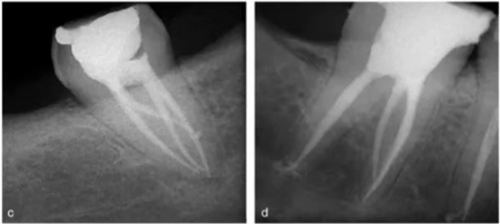

異于雙根的下頜第一磨牙的解剖形態(tài)變異主要為存在一個(gè)額外的位于遠(yuǎn)舌側(cè)【radix entomolaris(RE)】或近頰側(cè)【radix paramolaris(RP)】的牙根(圖 13)。在白種人和非洲人中發(fā)生這種牙根異常形態(tài)的概率不超過 5%,然而在黃種人中(比如中國(guó)人、因紐特人、印第安人)遠(yuǎn)舌根發(fā)生率在 5%至超過 30%之間。位于頰側(cè)的近頰根罕見,發(fā)生率低于 0.5%(。遠(yuǎn)舌根的外形大小可從小圓錐形變化至正常長(zhǎng)度和根管的“成熟的”牙根。

一般來說,遠(yuǎn)舌根比遠(yuǎn)頰根和近中根小,可能獨(dú)立于或部分融合于其他牙根。臨床治療過程中,當(dāng)懷疑存在額外的牙根時(shí),需要根據(jù)準(zhǔn)確的放射學(xué)診斷、臨床檢查、開髓洞型預(yù)備進(jìn)行判斷。在術(shù)前的放射片中,若遠(yuǎn)中根輪廓或根管的視野或外形不清楚,可能表明存在“隱藏的”牙根。在近中或遠(yuǎn)中成 30 度角的方向上拍攝第二張放射片,通??梢燥@示遠(yuǎn)舌根的輪廓。